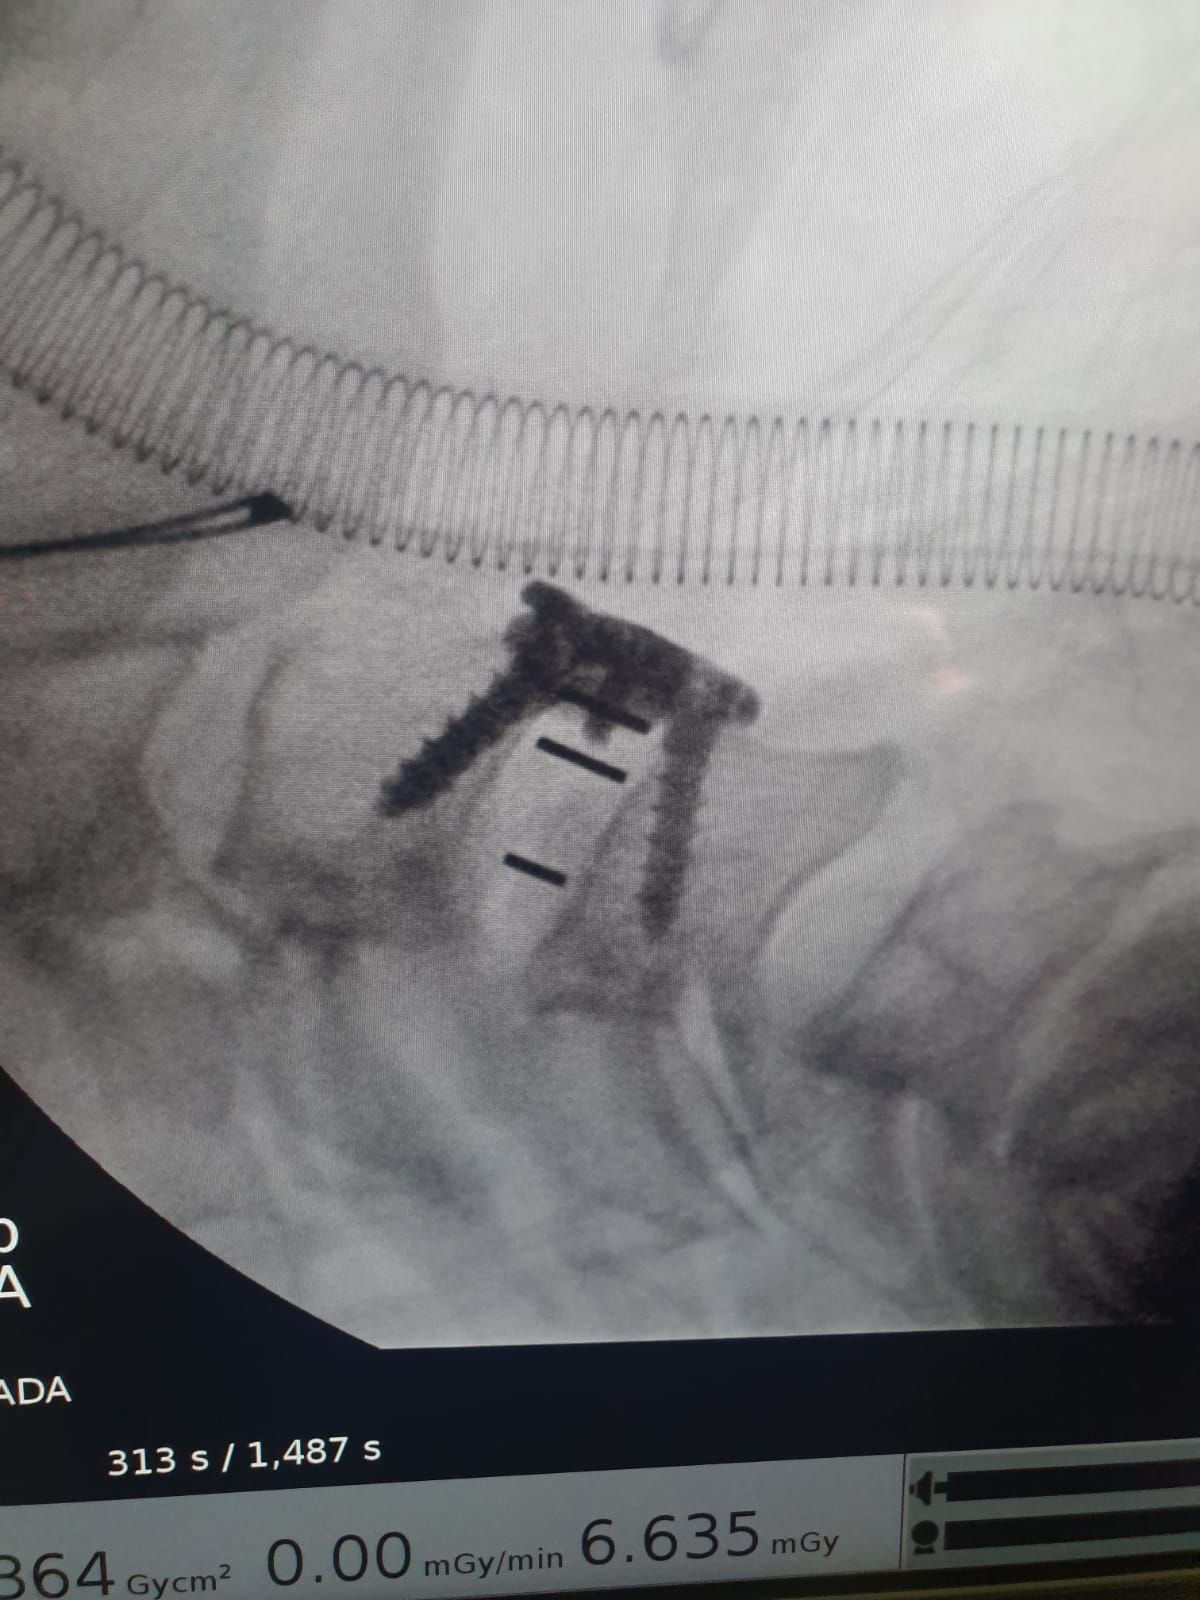

- Cirugía de Columna

- Cirugía Mínima Invasiva de Columna

Sin especificarArtrodesis cervical anterior